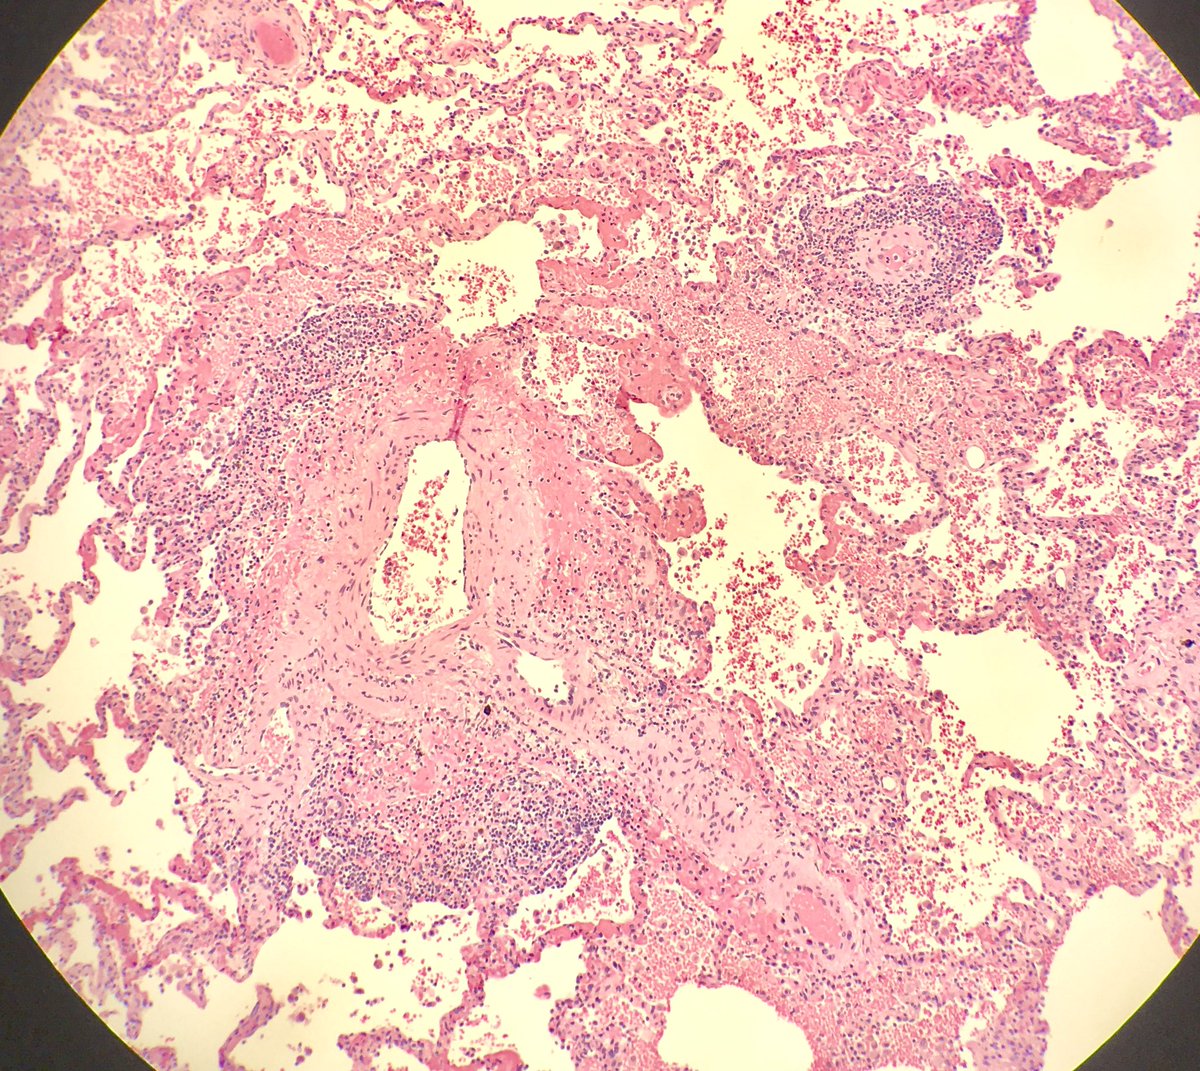

Fall from height: blunt force injuries including pulmonary contusions: interstitial and alveolar hemorrhage, damaged bronchioles and vessels with hemorrhage in the walls. Fat emboli can be seen (femoral shaft fracture x 2) #pulmonarypath #lungpath #forensics #forensicpath

seattlequinns's tweet image. Fall from height: blunt force injuries including pulmonary contusions: interstitial and alveolar hemorrhage, damaged bronchioles and vessels with hemorrhage in the walls. Fat emboli can be seen (femoral shaft fracture x 2) #pulmonarypath #lungpath #forensics #forensicpath